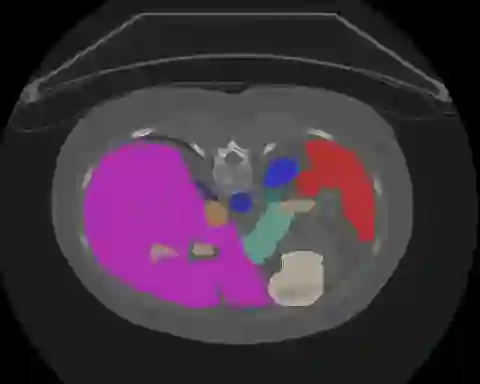

Transformers, the default model of choices in natural language processing, have drawn scant attention from the medical imaging community. Given the ability to exploit long-term dependencies, transformers are promising to help atypical convolutional neural networks (convnets) to overcome its inherent shortcomings of spatial inductive bias. However, most of recently proposed transformer-based segmentation approaches simply treated transformers as assisted modules to help encode global context into convolutional representations without investigating how to optimally combine self-attention (i.e., the core of transformers) with convolution. To address this issue, in this paper, we introduce nnFormer (i.e., Not-aNother transFormer), a powerful segmentation model with an interleaved architecture based on empirical combination of self-attention and convolution. In practice, nnFormer learns volumetric representations from 3D local volumes. Compared to the naive voxel-level self-attention implementation, such volume-based operations help to reduce the computational complexity by approximate 98% and 99.5% on Synapse and ACDC datasets, respectively. In comparison to prior-art network configurations, nnFormer achieves tremendous improvements over previous transformer-based methods on two commonly used datasets Synapse and ACDC. For instance, nnFormer outperforms Swin-UNet by over 7 percents on Synapse. Even when compared to nnUNet, currently the best performing fully-convolutional medical segmentation network, nnFormer still provides slightly better performance on Synapse and ACDC.